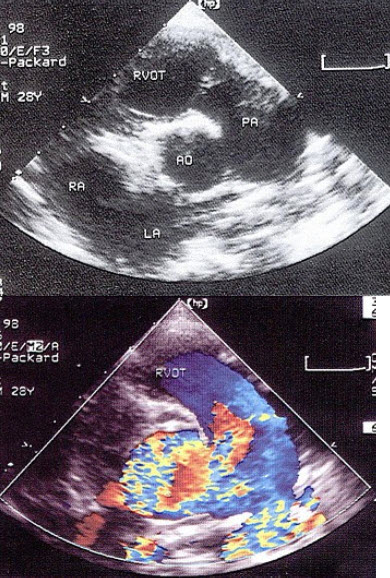

104、单项选择题

如图,初步超声诊断为()

A.二尖瓣返流

B.三尖瓣返流

C.主动脉瓣返流

D.肺动脉瓣返流

E.二尖瓣狭窄

105、单项选择题 指出下列正常肢体静脉的多谱勒超声表现哪项是错误的()